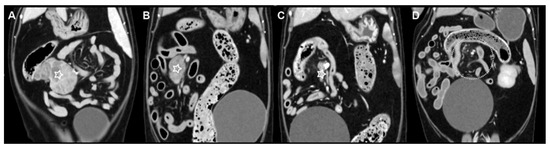

Multicentric Round Cell Neoplasia with Plasmacytic Differentiation in a Cat with Systemic Progression: Multimodal Imaging and Treatment Response

Plasma cell neoplasia is uncommon in cats, and multicentric nodal-predominant involvement has not been well characterized. This report describes a multicentric round cell neoplasia with plasmacytic differentiation in a 14-year-old Domestic Shorthair cat, emphasizing multimodal imaging features and treatment response. Contrast-enhanced computed tomography [...] Read more.

Plasma cell neoplasia is uncommon in cats, and multicentric nodal-predominant involvement has not been well characterized. This report describes a multicentric round cell neoplasia with plasmacytic differentiation in a 14-year-old Domestic Shorthair cat, emphasizing multimodal imaging features and treatment response. Contrast-enhanced computed tomography and magnetic resonance imaging were performed for staging and longitudinal assessment. Cytomorphology supported plasmacytic differentiation, and flow cytometry did not demonstrate an immunophenotype consistent with conventional B- or T-cell lymphoma. Because histopathology, immunohistochemistry, bone marrow evaluation, and assessment for monoclonal gammopathy were not performed, definitive classification was not possible; however, cytomorphology supported plasmacytic differentiation, with plasma cell neoplasia remaining an important diagnostic consideration. A hypofractionated radiotherapy protocol (36 Gy in six fractions) combined with systemic chemotherapy was administered. Serial imaging demonstrated complete radiologic resolution of the irradiated mass, whereas non-irradiated presumed nodal lesions progressed and an extradural spinal lesion subsequently developed. These findings highlight the capacity of round cell neoplasia with plasmacytic differentiation to mimic lymphoma on imaging and illustrate the dissociation between effective local control and ongoing systemic progression. Full article

(This article belongs to the Special Issue Abdominal Imaging in Small Animals: New Insights)

Show Figures

Figure 1